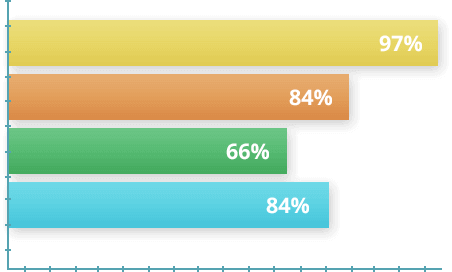

Pada tahun 2014, penelitian dilakukan dengan melibatkan 1.700 sukarelawan yang didiagnosis menderita hipertensi dengan berbagai tingkat keparahan. Tergantung pada kondisi klinis awal mereka, peserta menggunakan Artinormee secara konsisten selama periode 30 hingga 90 hari. Pada akhir penelitian, statistik menunjukkan hasil yang signifikan dalam mengendalikan hipertensi.

97% pengguna melaporkan penurunan tekanan darah yang signifikan dalam beberapa minggu pertama penggunaan.

84% menstabilkan tekanan darah mereka pada tingkat ideal hanya dengan satu botol produk.

66% pengguna mampu mengurangi dosis obat mereka di bawah pengawasan medis setelah menyelesaikan perawatan.

84% pengguna melaporkan peningkatan energi dan kesejahteraan dibandingkan dengan periode sebelum memulai perawatan.